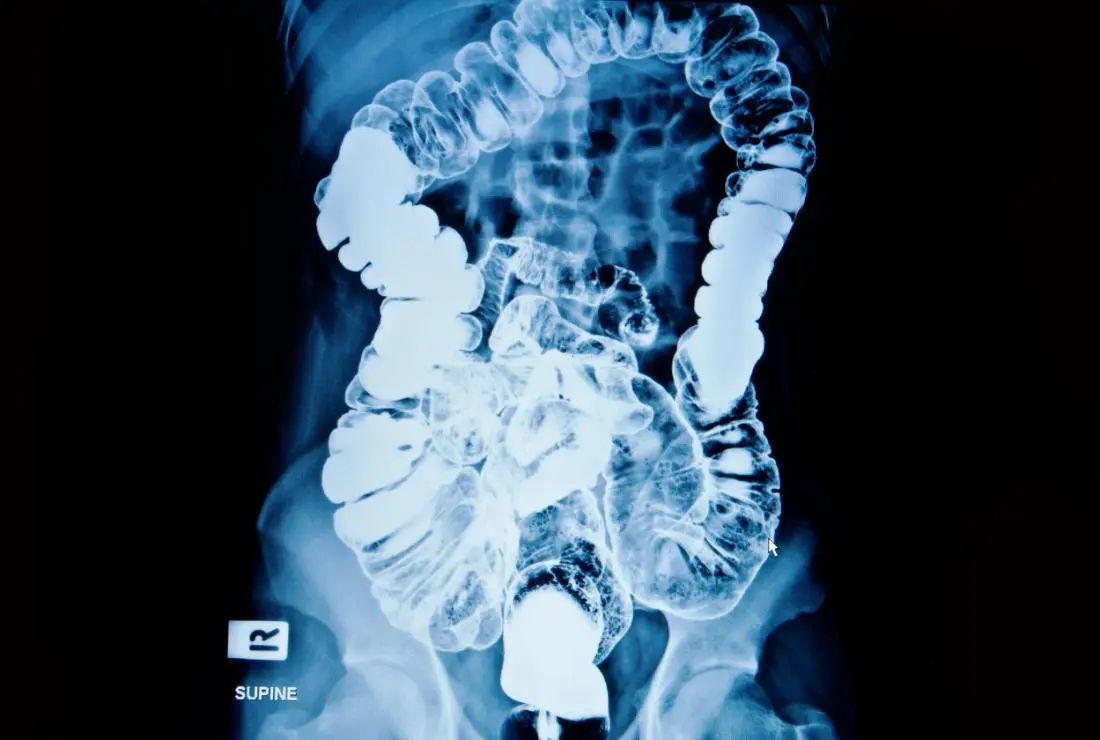

Digital X-Ray Services